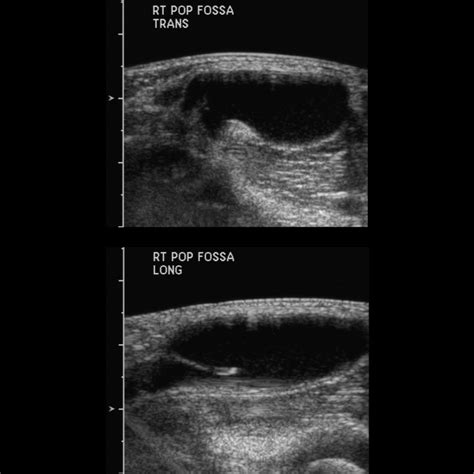

Instead of resorting to a Bible Cyst pop, it is recommended to consult with a healthcare professional. Medical practitioners can provide a formal diagnosis, often using transillumination—shining a light through the cyst—to confirm it is fluid-filled rather than a solid mass.